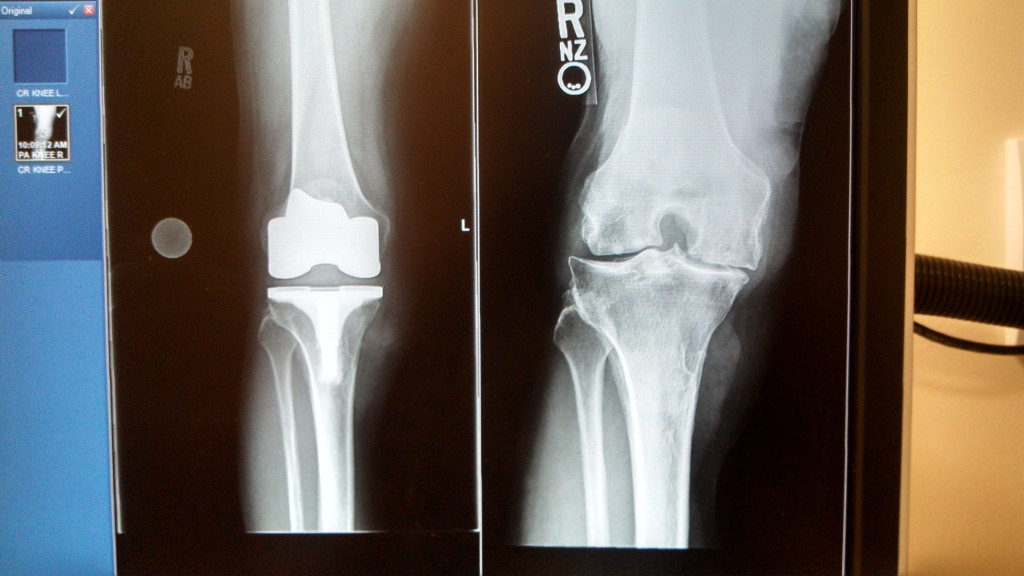

My mom had both of her knees replaced six weeks apart and she couldn’t have been happier. Prior to the first surgery (right knee) on 08/10/18 at HSS she was very scared and often questioned if she made the right decision to have her damaged knees replaced because of the pain associated with surgery and weeks of rehab. She is from Ghana and barely understands a word of English but after meeting her HSS surgeon, who took his time and managed to explain the procedure and the possible outcome to her understanding, she couldn’t wait. He did such a great job on her she was surprised she could walk without the help of a walker just after 4 weeks. The left knee was done on 9/28/18. She has a made marked improvement and she is happy with the result thus far. Today, we met her surgeon for a follow-up and when she saw the before and after x-ray picture of both legs she was all smiles. She felt she couldn’t thank the HSS team enough for the wonderful job they did on her. He appears compassionate and caring she said to me and that she is glad and lucky she had him as her orthopedic surgeon. Her surgeon is awesome and I will definitely recommend him to anyone who needs a knee replacement surgery. Thank you.